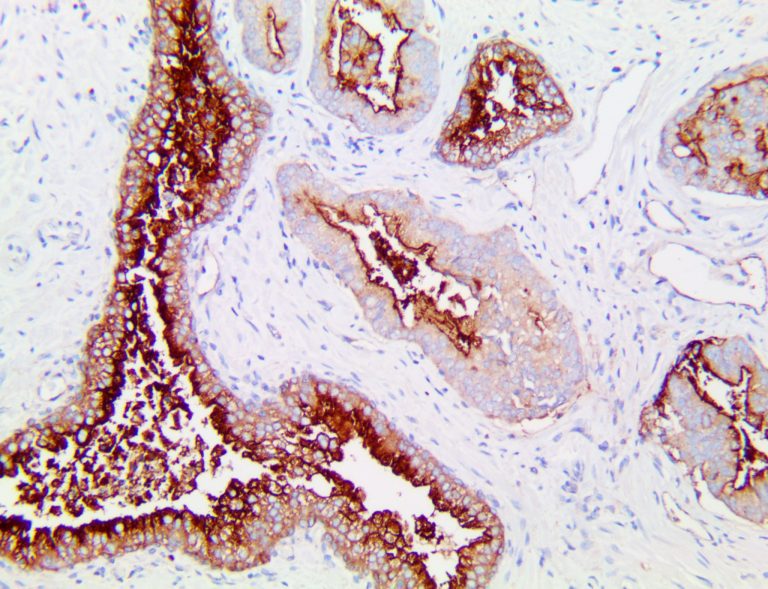

The first cytokines released are interleukin 1β (IL-1β) and tumor necrosis factor-α (TNF-α), which attract a variety of circulating white blood cells (WBCs) to the infection site, including neutrophils, monocytes, macrophages, and natural killer (NK) cells. This response, along with the antipathogenic chemicals released by these cells (i.e., complement), comprise the innate immune response. These cells directly attack the invading pathogen and also release additional cytokines, chief among them interleukin-1 and 6 (IL-6). IL-6 is essential for invoking the adaptive immune response, which calls T-cells, B-cells, and T helper (Th) cells to the infection site. IL-6 also stimulates further recruitment, proliferation and activation of macrophages.

This activation induces inflammatory monocytes to highly express IL-6, starting a localized and then systemic cascade effect that results in hyperproduction of IL-6, which accelerates the inflammatory process. Because IL-6 also increases vascular permeability, excessive levels cause blood vessels to become very leaky. This, along with clotting factors released from vascular endothelial cells, stimulates the coagulation cascade, resulting in microthrombosis (tiny clots), which leads to ischemia and tissue death of the kidney, intestines, heart, liver, brain and extremities.